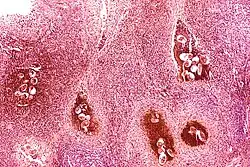

Certain bacterial infections also increase the risk of cancer, as seen in Helicobacter pylori-induced gastric carcinoma.[79] The mechanism by which H. pylori causes cancer may involve chronic inflammation or the direct action of some of the bacteria's virulence factors.[80] Parasitic infections strongly associated with cancer include Schistosoma haematobium (squamous cell carcinoma of the bladder) and the liver flukes, Opisthorchis viverrini and Clonorchis sinensis (cholangiocarcinoma).[81] Inflammation triggered by the worm's eggs appears to be the cancer-causing mechanism. Certain parasitic infections can also increase the presence of carcinogenic compounds in the body, leading to the development of cancers.[82] Tuberculosis infection, caused by the mycobacterium M. tuberculosis, has also been linked with the development of lung cancer.[83]